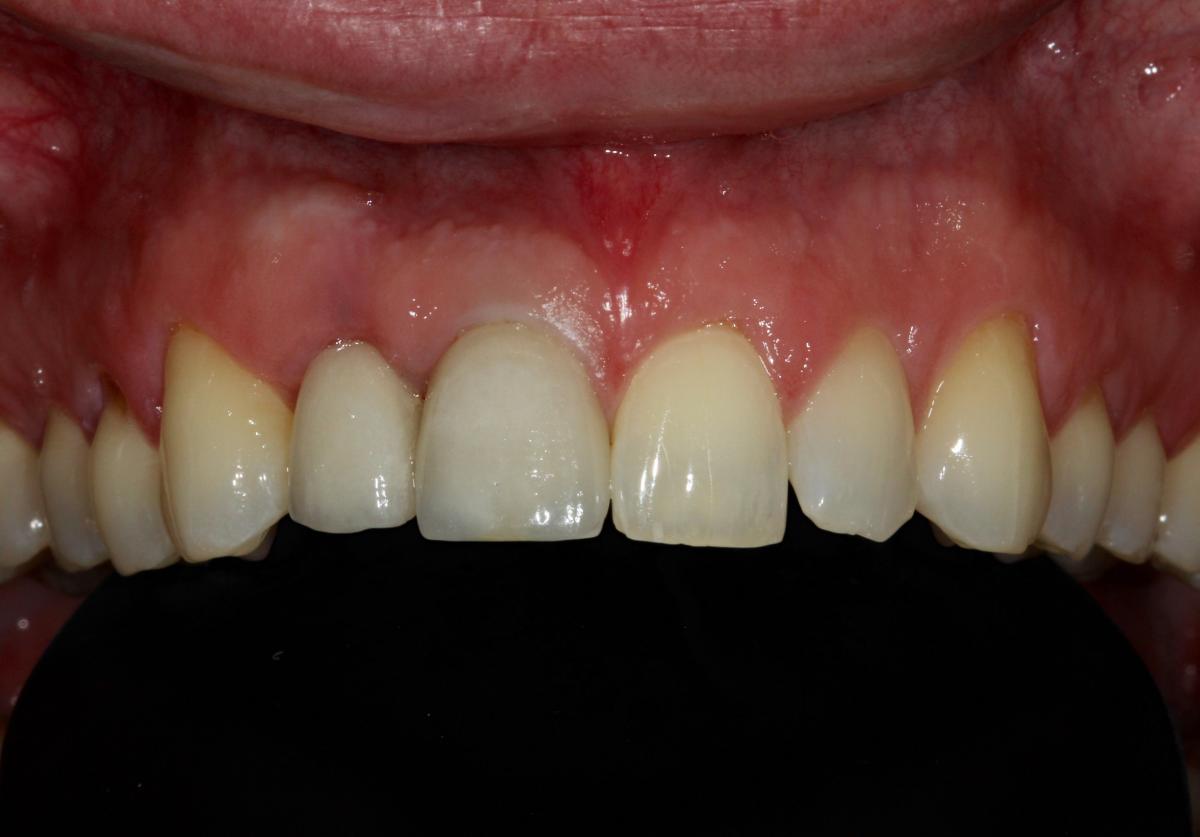

Missing teeth and loose dentures make many people avoid social settings because they are too self-conscious about their appearance. Current dental procedures, however, replace everything from a single missing tooth to a completely missing arch. Ask your dentist or dental specialist about the different dental options that are available to you. Don’t let another day go by without taking this important first step to restoring your confidence and your smile!